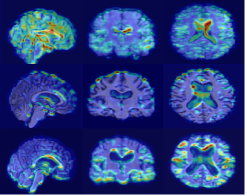

Refer to caption

(a) Original sMRI

(b) MixStyle

(c) EM1

(d) EM2

AIBL

(e) Original sMRI

(f) MixStyle

(g) EM1

(h) EM2

OASIS

(i) Original sMRI

(j) MixStyle

(k) EM1

(l) EM2

Figure 3: Grad-CAM visualizations on 3D sMRI samples across cohorts. The figure presents NC, MCI and AD subjects from ADNI (top row), AIBL (middle row), and OASIS (bottom row). For each cohort, columns show: original sMRI scans, MixStyle baseline, EM1 based on mean, standard deviation, and skewness, and EM2 extending EM1 with kurtosis.

Grad-CAM visualizations in Fig. 3 show that, compared to MixStyle, the proposed EM variants produce more stable and focused activations within cortical and subcortical regions commonly affected by AD. EM1 provides the clearest localization, reducing noisy responses outside brain tissue and highlighting disease-relevant areas more consistently. EM2 shows a similar trend, though its attention maps are slightly more diffuse. These improvements are most evident in ADNI and AIBL, while OASIS shows smaller but consistent gains. Overall, incorporating higher-order moments encourages the model to focus on more anatomically meaningful structures.